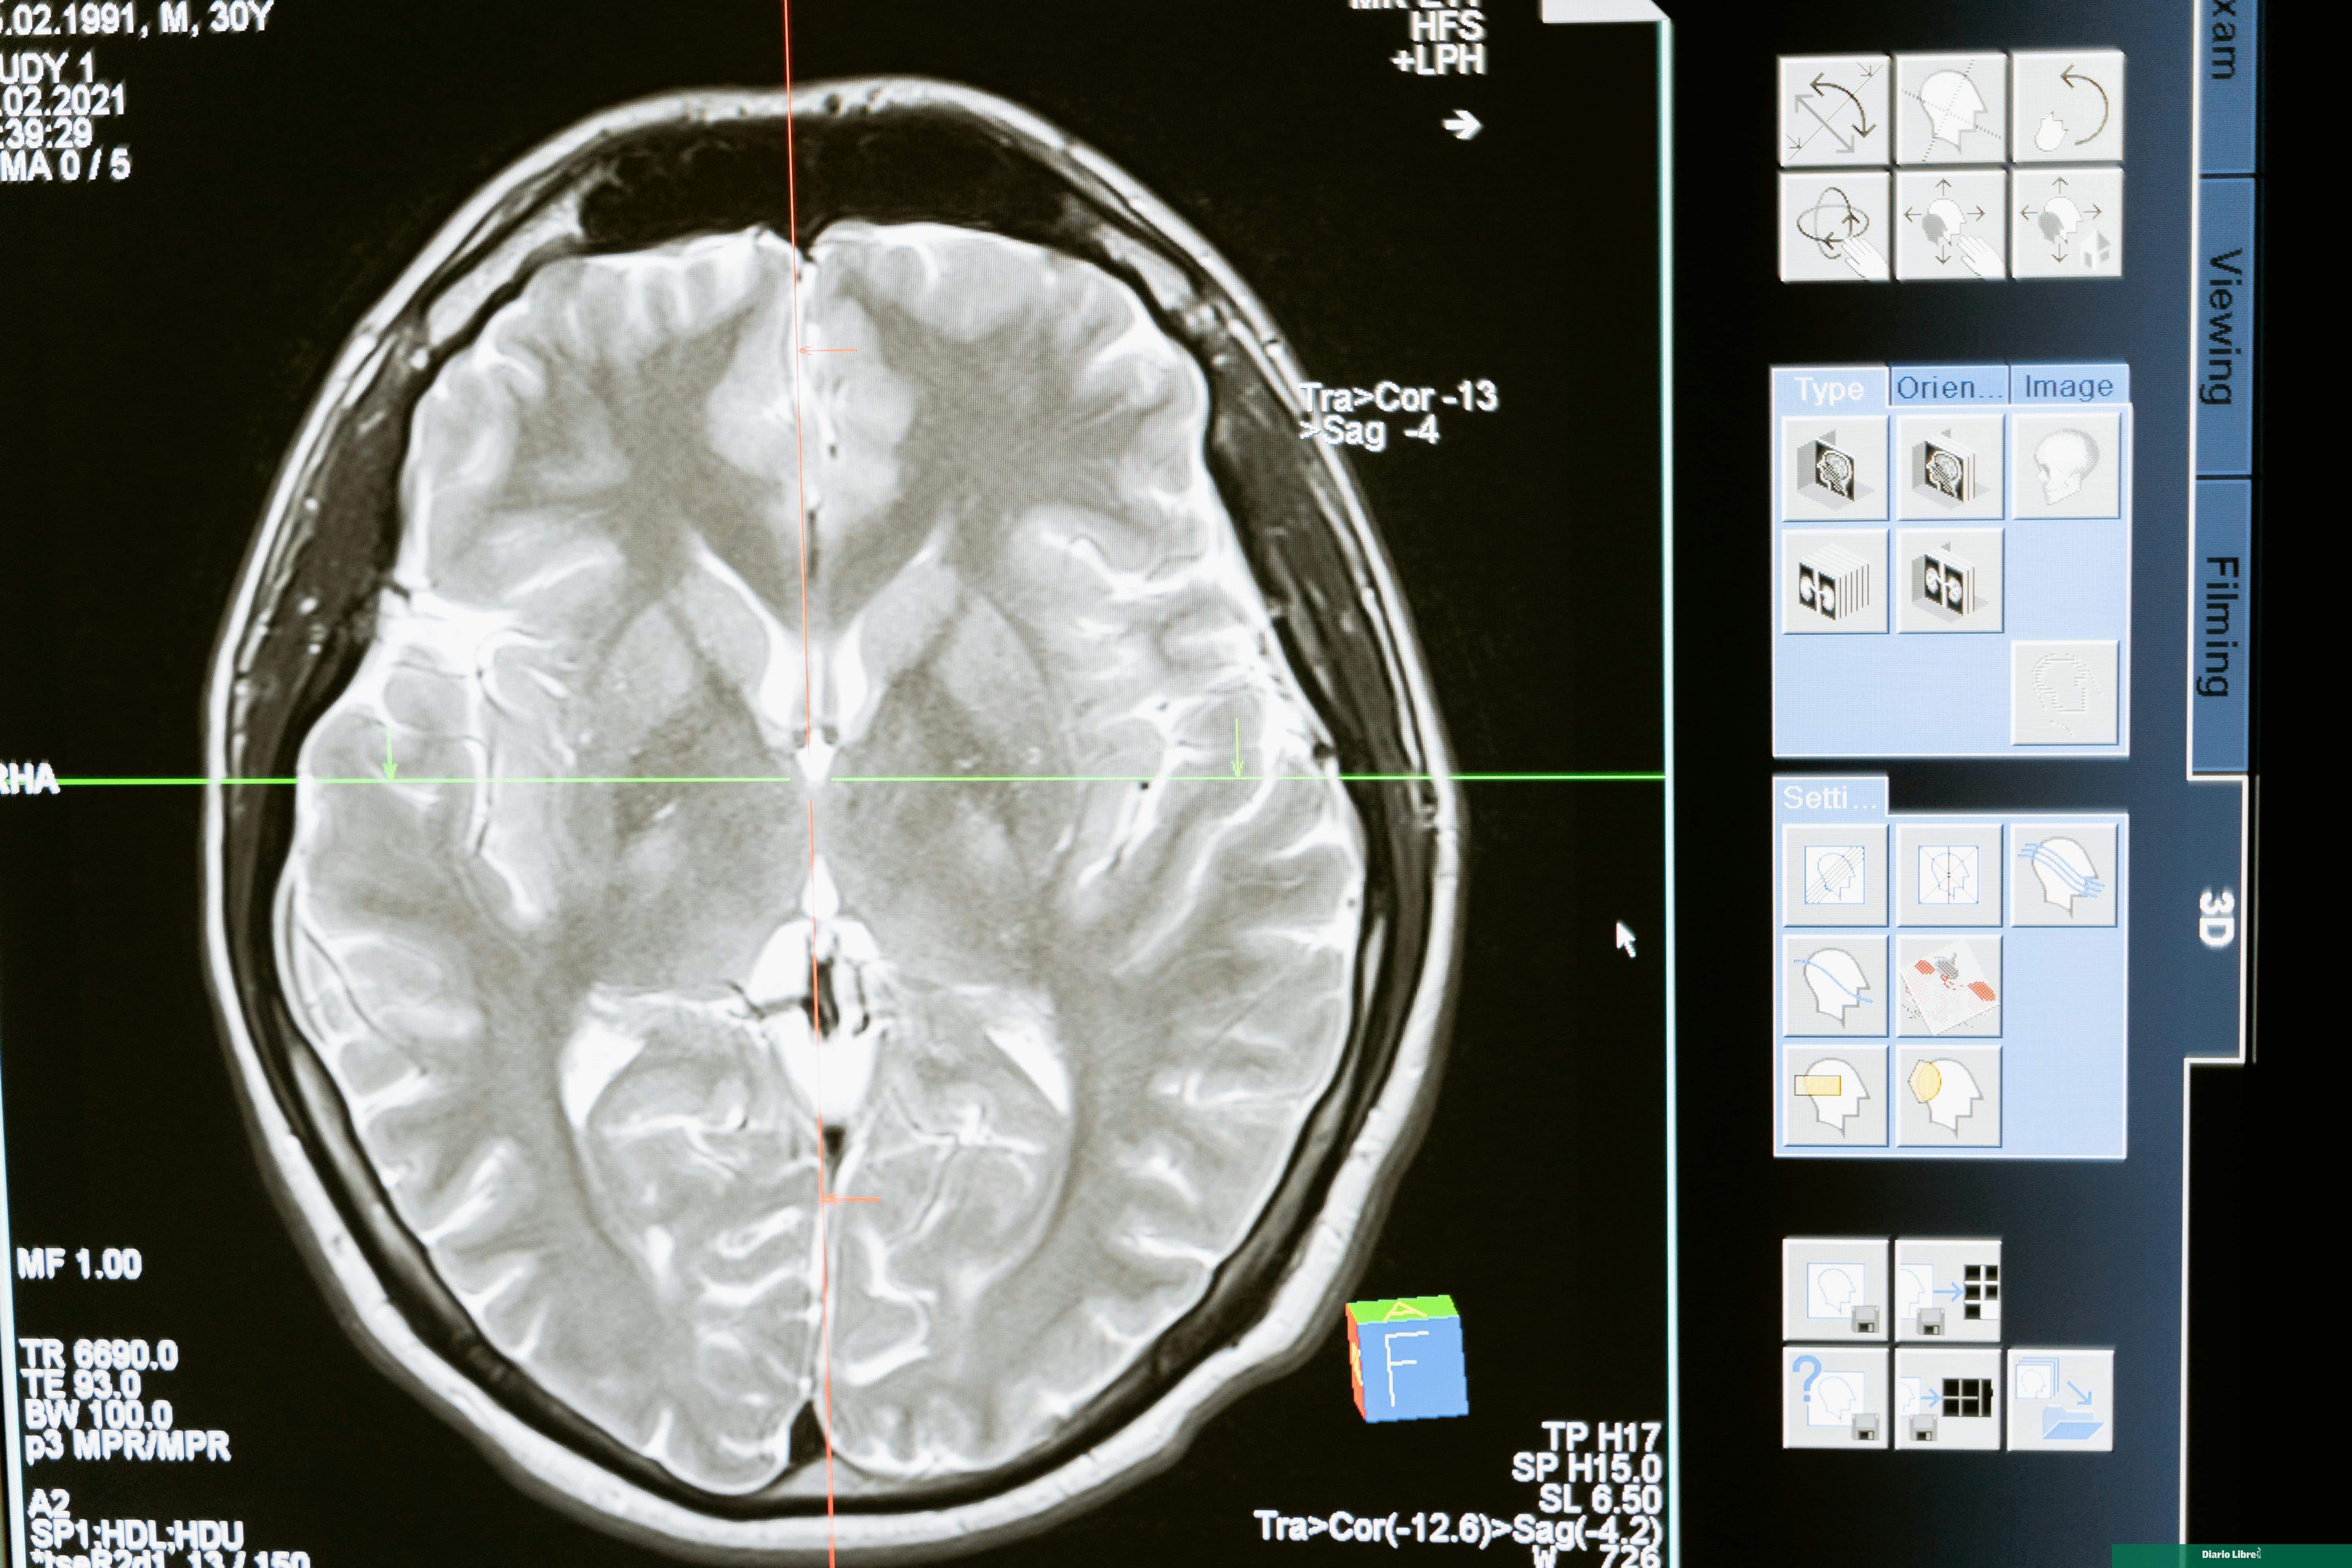

Los investigadores han recurrido a organoides cerebrales humanos (modelos en miniatura del cerebro cultivados en laboratorio) para averiguar cómo esa exposición al plomo en la antigüedad pudo afectar al desarrollo cerebral.